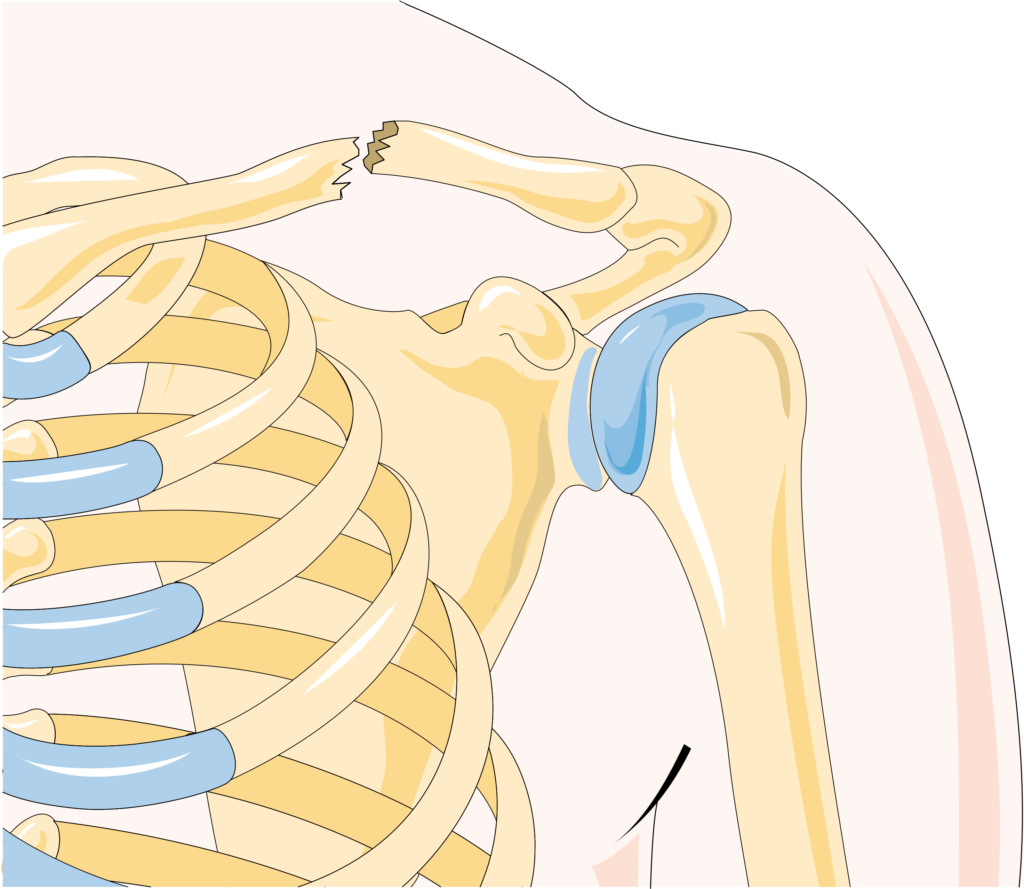

L’infortunio può anche avvenire a causa di un trauma o colpo diretto sulla clavicola da parte di un avversario, per esempio in sport come il calcio. Sulle fratture laterali, il trauma è solitamente diretto verso l’esterno della spalla, come succede anche negli infortuni a danno dell’articolazione acromion-claveare (AC joint) e clinicamente può sembrare al primo approccio come una diastasi della articolazione AC. Le lesioni di questo sito sono divise in mediali e laterali rispetto al legamento coraco-clavicolare. Un ulteriore classificazione è basata sulla suddivisione della clavicola anatomicamente in tre parti: mediale, centrale e distale.

Il gonfiore e il mal allineamento sono facili da localizzare.2 Se il paziente ha una frattura del moncone laterale, il gonfiore, il dolore e il probabile mal allineamento sono localizzati intorno all’articolazione acromion-claveare.

La clavicola solitamente si frattura nel terzo medio con il moncone esterno che si dispone inferiormente e il mediale superiormente. Questo tipo di lesione è spesso estremamente dolorosa. All’esame obiettivo, si manifesta con dolorabilità, gonfiore e deformità ossea palpabile. Con l’accorciamento della clavicola o con un aumento del grado di angolazione dei monconi, la scapola assumerà una posizione di tilt anteriore. Le fratture composte o con un minimo spostamento (meno di 1 cm) sono facili da trattare, e guariscono solitamente in poche settimane.

Il fissaggio chirurgico è indicato solo se c’è la presenza di frattura esposta o di un accorciamento maggiore di 1-2 cm. La non-unione dei monconi può svilupparsi anche a causa della formazione di pseudoartrosi fibrosa. In questo caso, infatti, si preferisce la chirurgia attraverso una riduzione open con fissazione interna con placca e bone chips per assicurare il mantenimento della lunghezza della clavicola.